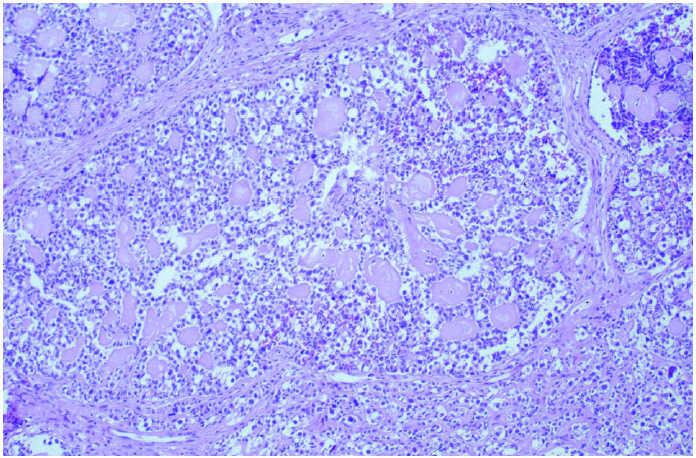

En la figura 7 se observa que el ovario izquierdo es una formación más pequeña, nodular e irregular en comparación con el anterior. A la sección muestra una tumoración en 2 nódulos con una superficie de corte homogénea que recuerda al ovario derecho, y otras áreas de aspecto espiculado y granular que corresponderían al gonadoblastoma (fig. 8). Microscópicamente, las secciones muestran una tumoración con un área similar al tumor del ovario derecho, disgerminoma, mientras que en otras presenta abundantes calcificaciones y nidos tumorales que se disponen en una formación típica que recuerda los folículos primitivos, con pequeñas acumulaciones de material eosinófilo acelular en su interior, similar a los cuerpos de Call-Exner. Por último, y de forma característica, se aprecian zonas calcificadas, lo que le confiere un aspecto granular (figs. 9-11).

Figura 9.Aspecto microscópico del gonadoblastoma con 2 áreas definidas, una que recuerda al disgerminoma y otra con calcificaciones y nidos tumorales.

Figura 10. Gonadoblastoma con acumulaciones de material eosinófilo en los nidos tumorales.

Figura 11.El gonadoblastoma se caracteriza histológicamente por la presencia de calcificaciones.